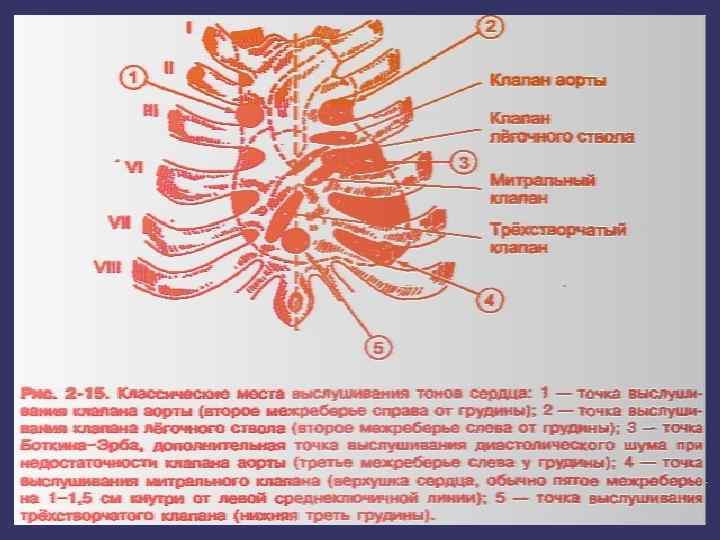

Митральды қақпақ (сол жақ жүрекше - қарыншалық қақпақ) төстің III қабырғамен түйіскен жерінде проекцияланады. Қолқа қақпағы төстің III қабырғаның сол және оң жақтарындағы шеміршектерінің бекіністерінің ортасынан жүргізілген сызықтың ортасында проекцияланады.

Жүрек қақпақтарының жазықтықта орналасуы

Жүрек ауруларында диагностикасы үшін аускультация әдіс маңызды болып табылады. Жүректің туа пайда болған және жүре пайда болған ұстамаларын анықтау үшін аускульттық картиналарын білу өте маңызды болып есептелінеді. Жүрек жиырылуы кезінде дыбыс эффектілері пайда болады – жүрек тонусы деп аталады және оны аускультация әдісі арқылы тыңдайды. Олардың пайда болуы қантамырларының қабырғаларының, жүрек клапандарының тербелістеріне, жүрек жиырылу кезіндегі қанның жүруі, миокард қабырғаларының тербелістеріне байланысты. Қалыпты жағдайда I-II